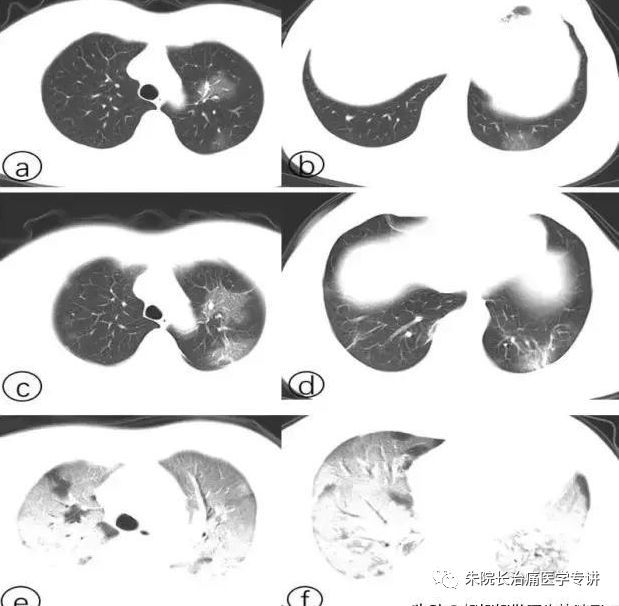

白肺早期症状

白肺早期症状相关图片